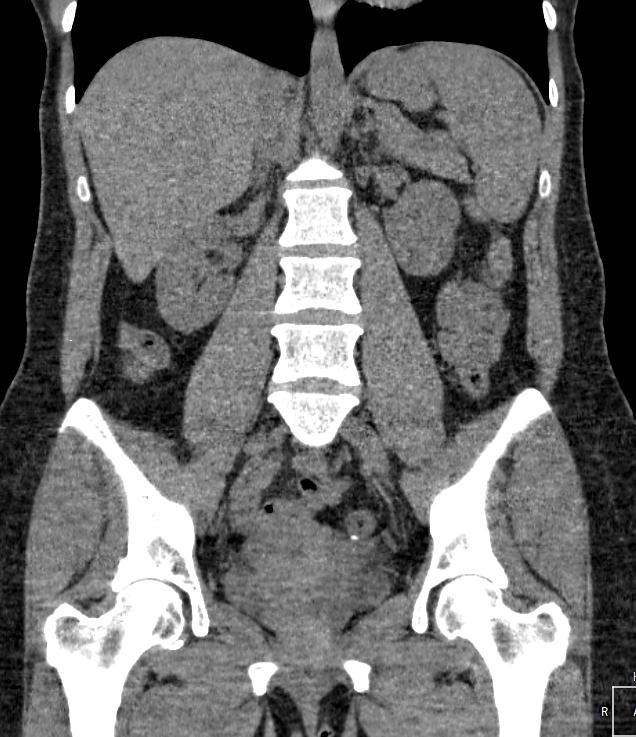

Методика КТ позволяет оценить анатомическое строение почек, надпочечников, состояние мочеточников и мочевого пузыря, кроме того, дает возможность визуализировать сосудистую систему и регионарные лимфатические узлы.

Сканирование применяется для выявления воспалительных заболеваний почек, чашечно-лоханочной системы, мочеточников и мочевого пузыря, также позволяет обнаружить конкременты на фоне мочекаменной болезни, диагностировать доброкачественные и злокачественные новообразования, точно классифицировать кистозные образования по системе Bosniak, что особенно важно для урологов и нефрологов, а также определить степень поражения регионарных лимфатических узлов. Кроме того, КТ используется для диагностики травматических повреждений органов мочевыделения, аномалий развития почечно-лоханочной системы, дает максимальную информацию для хирурга при планировании оперативного вмешательства.

Что показывает КТ почек, мочеточников, мочевого пузыря

- опущение почек;

- аномалии развития почек, мочетоников

- доброкачественные и злокачественные новообразования;

- камни (конкременты);

- уретероцеле

- сосудистую патологию (сосудисто-мочеточниковый конфликт, инфаркт почки);

- последствия оперативных вмешательств;

- увеличение лимфоузлов в брюшной полости, забрюшинном пространстве и малом тазу;

- травматические изменения

- патологии сосудов малого таза.